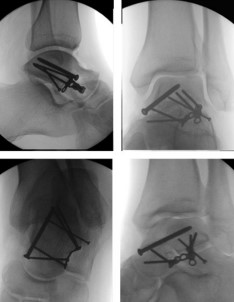

Методи фіксації: Сучасні методики включають остеосинтез гвинтами (канюльованими або кортикальними), пластинами або їх комбінацією. Анатомічна репозиція суглобових поверхонь є критичною для профілактики посттравматичного артрозу. Фіксація має забезпечувати достатню стабільність при мінімальному порушенні васкуляризації.

Артроскопічний контроль: Сучасні протоколи рекомендують артроскопічну асистенцію для верифікації якості репозиції суглобових поверхонь та видалення інтраартикулярних фрагментів.

Реабілітація

Післяопераційний період включає іммобілізацію протягом 6-12 тижнів без навантаження з поступовою активізацією під контролем рентгенографії. Фізіотерапія фокусується на відновленні амплітуди рухів, мʼязової сили та пропріоцепції. Повне навантаження типово дозволяється через 10-16 тижнів після травми при рентгенологічних ознаках консолідації.